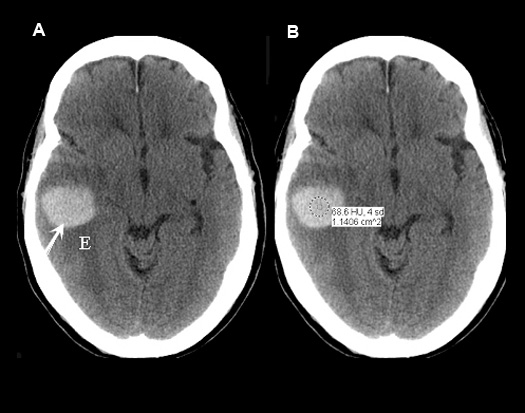

Case 6:

60 year-old patient with melanoma.

Imaging findings:

Figure 6 : Pre-contrast axial CT :

- Acute intracerebral hematoma within the right temporal lobe (arrow) with surrounding edema (E). Hounsfield units in the range of hemorrhage (68 H. U.).

Hemorrhage is from metastatic melanoma bleed. Acute hematoma is seen on non-contrast imaging as an area of high density.